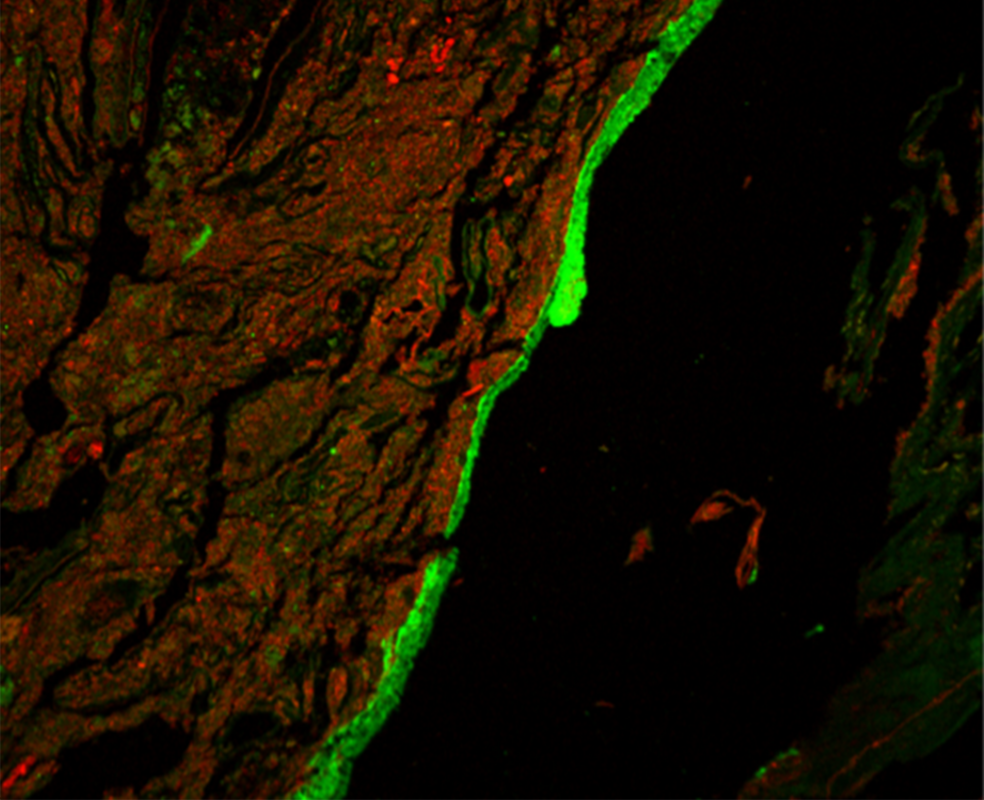

Слой слизи в толстой кишке отделяет хозяина от триллионов микробов, обитающих в просвете кишечника. Если этот слизистый барьер нарушается, бактерии могут проникнуть в кишечный эпителий хозяина и вызвать провоспалительную реакцию. Нарушение этого барьера является отличительной чертой ВЗК и, возможно, движущим фактором развития этих заболеваний. Терапия антибиотиками у мышей приводит к транслокации и поглощению бактерий в лимфатические узлы, дренирующие кишечник, и предрасполагает к развитию кишечного воспаления. Однако вопрос о том, повреждают ли антибиотики непосредственно слизистый барьер, остается неясным. В данном исследовании мы попытались проверить гипотезу о том, что антибиотики предрасполагают к развитию кишечного воспаления, нарушая слизистый барьер.

Мы обнаружили, что кратковременного перорального приема антибиотиков достаточно, чтобы нарушить разделение между хозяином и микробиотой в толстой кишке. Это явление было характерно для всех протестированных нами антибиотиков. Используя трансплантацию фекальной микробиоты и секвенирование РНК с последующим машинным обучением, мы пришли к выводу, что влияние ванкомицина на слизистый барьер не может быть перенесено на безмикробных мышей только за счет трансплантации микробиоты. Вместо этого мы обнаружили, что ванкомицин может препятствовать секреции слизи в толстой кишке независимым от микробиоты образом, вызывая ER-стресс (стресс эндоплазматического ретикулума) в клетках толстой кишки.